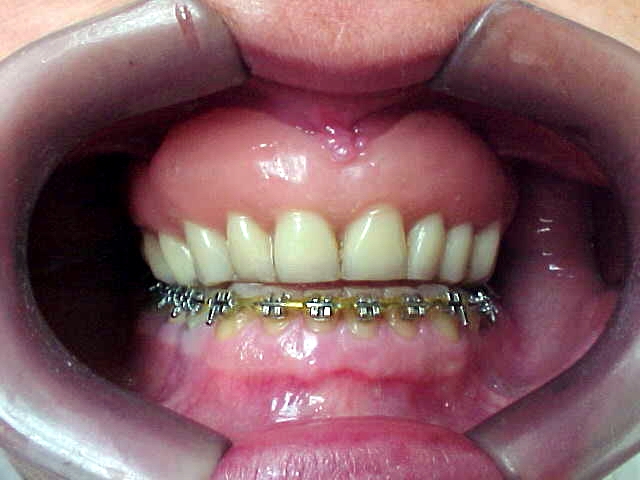

Aumento posterior para facilitar mecânica ortodôntica no arco inferior

Aparelho ortodôntico instalado